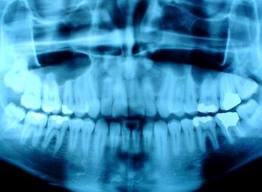

Los avances tecnológicos con el fin beneficiar la practica endodóntica han creado nuevos sistemas tratando de superar la radiografía convencional (RC) dentro de los cuales se encuentra la RadioVisioGrafía (RVG). Son muchos los estudios que se han realizado comparando estos dos sistemas exaltando sus ventajas y desventajas.

Las radiografías son necesarias antes durante e inmediatamente después del tratamiento endodóntico, y para evaluar periódicamente el éxito o fracaso de la terapia. Por lo tanto son requeridas repetidas exposiciones a las dosis de radiación. Muchos investigadores han sugerido los efectos deletéreos por radiaciones excesivas y repetitivas dentro de las cuales se encuentran: mucositis, serostomia, sialoadenitis, destrucción de la substancia del diente, necrosis de las células pulpares reabsorción radicular, retardo del desarrollo dental, inhibición de la erupción, anodoncia y osteoradionecrosis, como también anormalidades en el desarrollo del feto siendo el periodo de organogénesis el más sensitivo entre los 18 y 45 días de gestación. La RC nos da una imagen en dos dimensiones de un objeto de tres dimensiones, además para lograr calidad radiográfica se requiere de una precisa colocación y angulación del tubo de rayos X (16). Las radiografías convencionales son más comúnmente utilizadas para determinar la longitud de trabajo en la terapia endodontica. Dichas radiografías proveen una gran claridad y calidad de detalle para visualizar la punta de la lima en relación con el ápice radiográfico (17) (18). Una de las desventajas de la radiografía convencional en el tratamiento de conductos es el incremento en la radiación cuando múltiples exposiciones son necesarias cuando se está determinando la longitud de trabajo. Si se comparara con la RVG el tiempo de revelado también es una desventaja ya que interrumpe el tratamiento; la RVG se obtienen instantáneamente (19). Se han realizado algunos estudios en los que se ha encontrado que la RVG presenta menor resolución que la radiografía periapical convencional, Horner también confirmó que la RVG presenta una menor resolución al compararla con la RC, por otro lado Horner encontró que la RVG produce imágenes aceptables con una menor dosis de radiación al compararla con la convencional (17).

La radiovisiografía presenta ventajas tales como: permitir un ahorro de de tiempo , disminuir la necesidad de un cuarto oscuro, de película, de posicionador, de equipo de procesado y de el consumo de químicos; es más rápida al definir el ápice con reducción en la radiación, reduce el tiempo en el sillón, la interpretación de la imagen es más completa, la imagen puede ser variada en tamaño y contraste, puede ser impresa y puede ser guardada en el computador, tiene la habilidad de producir imágenes instantáneas (16) (20) (21). Se ha reportado que la RVG provee aproximadamente un 80% de reducción en la dosis de radiación en comparación con la RC (16) (22) (23), lo cual es resultado del corto tiempo de exposición y el incremento en la colimación que es permitida por el sensor pequeño (20) .

Se han realizado estudios en los que comparan la RVG con la radiografía convencional como medio diagnóstico para detectar lesiones periapicales que han sido creadas mecánicamente y se ha encontrado que la RC presenta mejor especificidad y la RVG mejor sensibilidad para detectar lesiones (23). En otro estudio similar reralizado por Mistak los resultados no presentaron diferencias estadísticamente significativas entre los dos sistemas utilizados(24). También se han realizado estudios comparando la RVG con la RC en la determinación de trabajo y no se han encontrado diferencias estadísticamente significativas, concluyendo que la RVG presenta igual valor a la RC en la determinación de la longitud de trabajo (25) (26). Se han encontrado otros reportes donde consideran que la RVG es mejor o igual que la radiografía convencional, pero que indudablemente presenta ventajas como la reducción en la dosis de radiación, en el tiempo del tratamiento, lo cual favorece a la RVG como sistema de imagen de escogencia (17), sin descartar que la radiografía intraoral da una excelente representación de las estructuras y son tan útiles como engañosas; por lo tanto lo más importante es determinar donde estamos situados para de ésta manera evitar errores.

SISTEMA INTRAORAL

En la odontología, la técnica digital se introdujo hace 10 años en forma de radiografías intraorales. El diagnóstico radiográfico es siempre invasivo, esto hace que el paciente rechase las radiografías o el odontólogo no las efectúe en las consultas de urgencia. Precisamente debido a las difíciles relaciones anatómicas en la zona de las raíces dentarias, el tiempo de tratamiento y las medidas endodónticas satisfactorias se correlacionan positivamente con el número de radiografías. Las ventajas de la nueva técnica digital son la escasa dosis de radiación, la disponibilidad inmediata de la radiografía, la representación de la imagen que permite adaptarse a la duda planteada, la renuncia considerable a materiales de consumo y el archivo electrónico con la formación de una base de datos dentro y fura de la clínica (10).

Una imagen digital se origina a través de un sensor de imagen que escoge punto por punto de un computador y cada punto dependiendo de la intensidad radiográfica allí registrada coordina un grado de intensidad. esta correlación de grados o digitalización es la condición previa para la preparación de la imagen en el ordenador. En sistemas para radiografías dentales intraorales se distinguen las radiografías directas e indirectas. En la grabación directa, una cámara semiconductora transforma en la boca del paciente la distribución de rayos X en una señal electrónica que se introduce en el ordenador a través de un cable y se representa sobre un monitor sin demora(10). La radiovisiografía (RVG) y Flash Dent son un ejemplo como también sistemas como como el Sens-A-Ray ( Regam Medical Systems AB, Sundsvall, Sweden) y vixa ( Visualix, Med Cam, Vido Dental Products, New Image) (14). En cuanto a la radiovisiografía se ha encontrado que no muestra una diferencia estadísticamente significativa comparada con la radiografía convencional y que se prefiere su uso debido a la reducción en la dosis de radiación (15). En el procedimiento indirecto, una placa de almacenamiento sirve de almacenamiento provisional de la imagen, llega al ordenador sin relaciones de cables y, después de la irradiación, se selecciona en un aparato para leer la información (10).